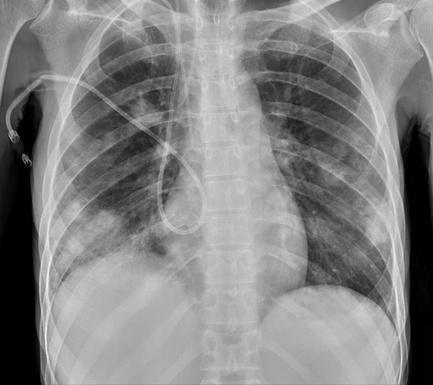

W badaniach laboratoryjnych stwierdzono wysokie wskaźniki stanu zapalnego: CRP 550 mg/l, prokalcytoninę 61 ng/ml, nieznacznie podwyższoną leukocytozę, ciężką niedokrwistość normocytarną, znaczne zaburzenia elektrolitowe, podwyższone metabolity azotowe i enzymy wątrobowe, podwyższony poziom ferrytyny i D-dimerów oraz niedobory białkowe. Obraz RTG klatki piersiowej sugerował rozsiane zmiany zapalne i ropnie. Podczas hospitalizacji pobrano 4 komplety posiewów krwi obwodowej oraz posiewy z cewnika centralnego, który na czas oczekiwania na wyniki został wyłączony z użytkowania i zabezpieczony taurolidyną. W posiewach wykryto Staphylococcus aureus MSSA.

Zadecydowano o usunięciu wkłucia W trakcie pobytu obserwowano spadki ciśnienia tętniczego, włączono noradrenalinę we wlewie ciągłym do wkłucia centralnego. Wkłucie utrzymano około 2 tygodnie. Następnie wykonano TK klatki piersiowej i jamy brzusznej, które wykazało obustronne plamiste i guzkowe ogniska konsolidacji miąższu płuc oraz rozsiane zmiany torbielowato-płynowe w górnych płatach obu płuc, przemawiające za ropniami. W dolnych płatach obu płuc widoczne były grubościenne jamy ze zmianami martwiczymi Dodatkowo stwierdzono wrzecionowaty ropień przestrzeni podobojczykowej lewej, rozległy palczasty ropień ponad mięśniem naramiennym i stawem barkowo-obojczykowym bez penetracji dostawowej oraz zakrzepicy w prawej żyle szyjnej zewnętrznej, obu żyłach ramienno-głowowych i obu żyłach biodrowych wspólnych. Ze względu na zwiększone ryzyko zatorowości podjęto decyzję o usunięciu wkłucia centralnego. Końcówkę cewnika przesłano do badania mikrobiologicznego, które wykazało obecność Candida glabrata